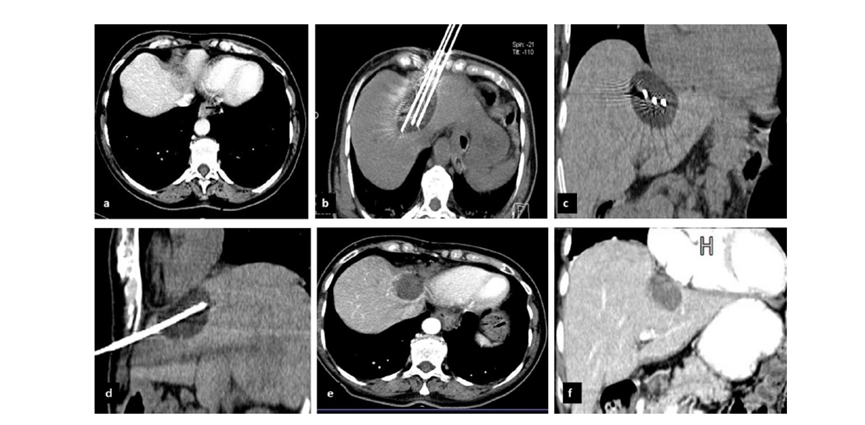

62岁女性,肝转移(卵巢癌)肿瘤的完全消融病例

(a)轴向CT显示病变位置毗邻心脏和上腔静脉(黑色箭头)。

(b)术中轴向CT扫描:使用三个冷冻探针。

(c)冠状面和(d)矢状面显示冰球毗邻心包。

1个月后的轴向(e)和冠状位(f)增强CT扫描显示低密度区域,由于肉芽组织反应引起的边缘增强。